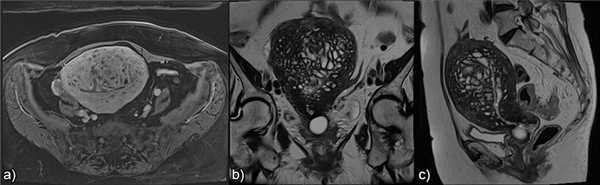

![]()

Рис.4: Диффузный аденомиоз: а) сагиттальные и b) корональные T2 изображения, показывающие утолщение переходной зоны c образованием плохо отграниченной области с низкой интенсивностью сигнала, точечными гиперинтенсивными включениями.

Рис.5: Фокальный аденомиоз: а) сагиттальные T2, b) аксиальные T2 , с) аксиальные T1 3D FS изображения, показывающие фокальное асимметричное утолщение переходной зоны, образующее плохо отграниченную область с низкой интенсивностью сигнала, наличием в структуре мелких гиперинтенсивных на Т2 и Т1FS включений, представленных мелкими кровоизлияниями.